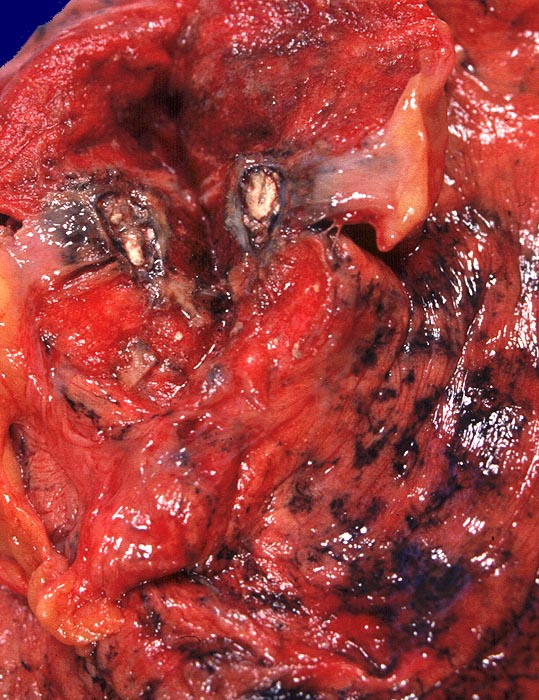

PathoPic ID 359 - alter tuberkulöser Primärkomplex

alter tuberkulöser Primärkomplex

Entzündung infektiös

Lunge

Kalkkreideherd im apikalen Oberlappen rechts.

Langjähriger Nikotinabusus. Zungenkarzinom bekannt seit einem Jahr. St.n. kleinzelligem Bronchuskarzinom vor 4 Jahren.